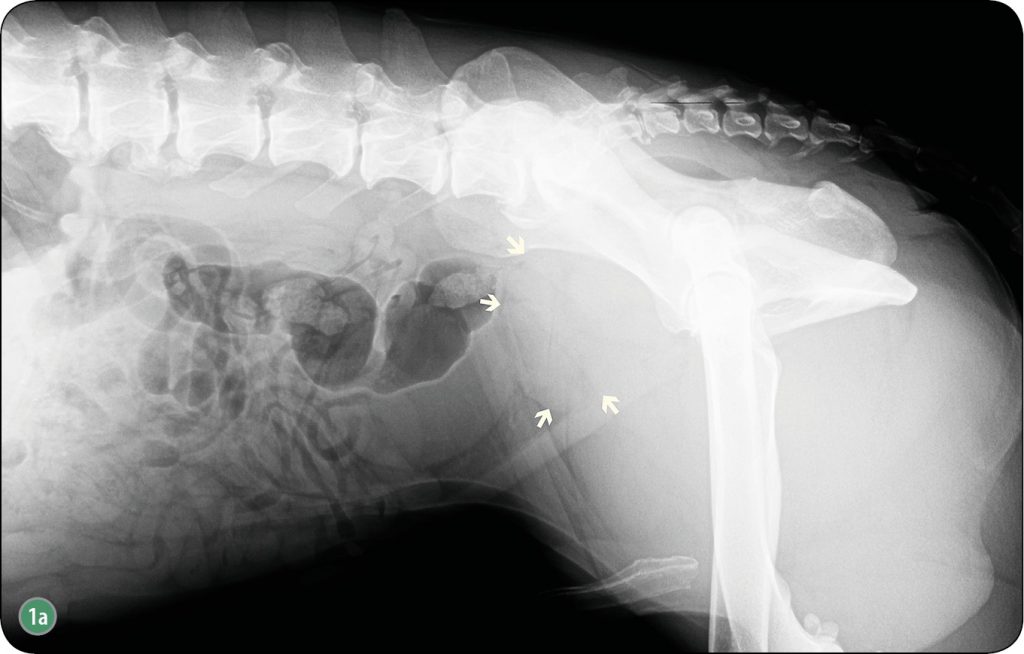

Zmieniony nowotworowo gruczoł krokowy ulega często znacznemu powiększeniu (ryc. 1a) (26). W takich przypadkach pęcherz moczowy ulega przemieszczeniu w kierunku doczaszkowym. Występuje także dogrzbietowe przemieszczenie okrężnicy ze zwężeniem jej światła (2, 4, 7, 8, 9, 26, 27). Analizując radiogramy, należy pamiętać, że do powiększenia gruczołu krokowego dochodzi również w innych procesach chorobowych, jak np. obecności ropni, dużych torbieli czy zapalenia, co wymaga poszerzenia diagnostyki o kolejne badania obrazowe, laboratoryjne czy też cytologiczne.

Choroba nowotworowa stercza prowadzi często do jego niesymetrycznego powiększenia (ryc. 1b). Należy jednak pamiętać, że brak symetrii płatów gruczołu krokowego także występuje w przypadkach dużych torbieli wewnątrzgruczołowych, które powodują deformację brzegu narządu (4 ,9, 26, 27). W agresywnych procesach nowotworowych gruczołu krokowego o charakterze intensywnie naciekającym w bezpośrednim sąsiedztwie stercza może dochodzić do lokalnego zapalenia. Na radiogramie brzegi gruczołu [...]